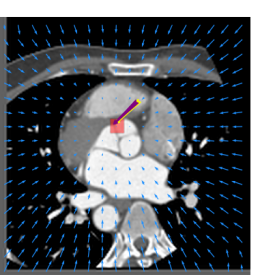

Finally, the proposed network was evaluated for the detection of five additional landmarks: the left coronary ostium, the bifurcation of the LM into the LAD and the LCx, and the origin of the left, non-coronary, and right aortic valve commissures (see Fig. 2). Fig 3 shows vector fields visualizing the predicted displacement vectors in three viewing planes in an image from the test set (for more results, see Appendix). Table 3 lists the Euclidean distance errors between the predicted landmark locations and the reference landmark locations. In addition, box-and-whiskers plots are shown in Fig 4. The best results were obtained for the origin of the right aortic valve commissure. Detection of the origin of the left aortic valve had the most narrow distribution. Outliers were seen during detection of the right ostium, the bifurcation of the LM, and the origin of the non-coronary, and the left aortic valve commissure.

Refer to caption Refer to caption Refer to caption

Figure 3: Vector fields visualizing the predicted displacement vectors in the axial, coronal, and sagittal plane in an image from the test set where detection of the right coronary ostium was performed. The magnitudes of the vectors should point at the right ostium, but they are rescaled for visualization purposes. The red squares indicate posterior probabilities larger than 0.5, obtained by the classification network for image patches. Reference and computed landmark annotations are indicated with a yellow and purple arrow, respectively.